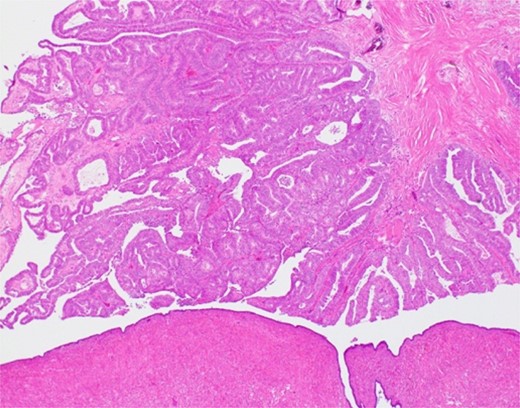

The histological findings with hematoxylin-eosin stain (H&E) revealed a cystic lesion with a very small and relatively dense stroma under the epithelium in the left paratubal region (Fig. 3). This stroma is CD10 positive in a small portion, suggesting the possibility of endometriosis (Fig. 4). Moreover, adenocarcinoma is arises from this cyst (Figs 5 and 6). There was no disseminated lesion in bilateral adnexa and uterus.